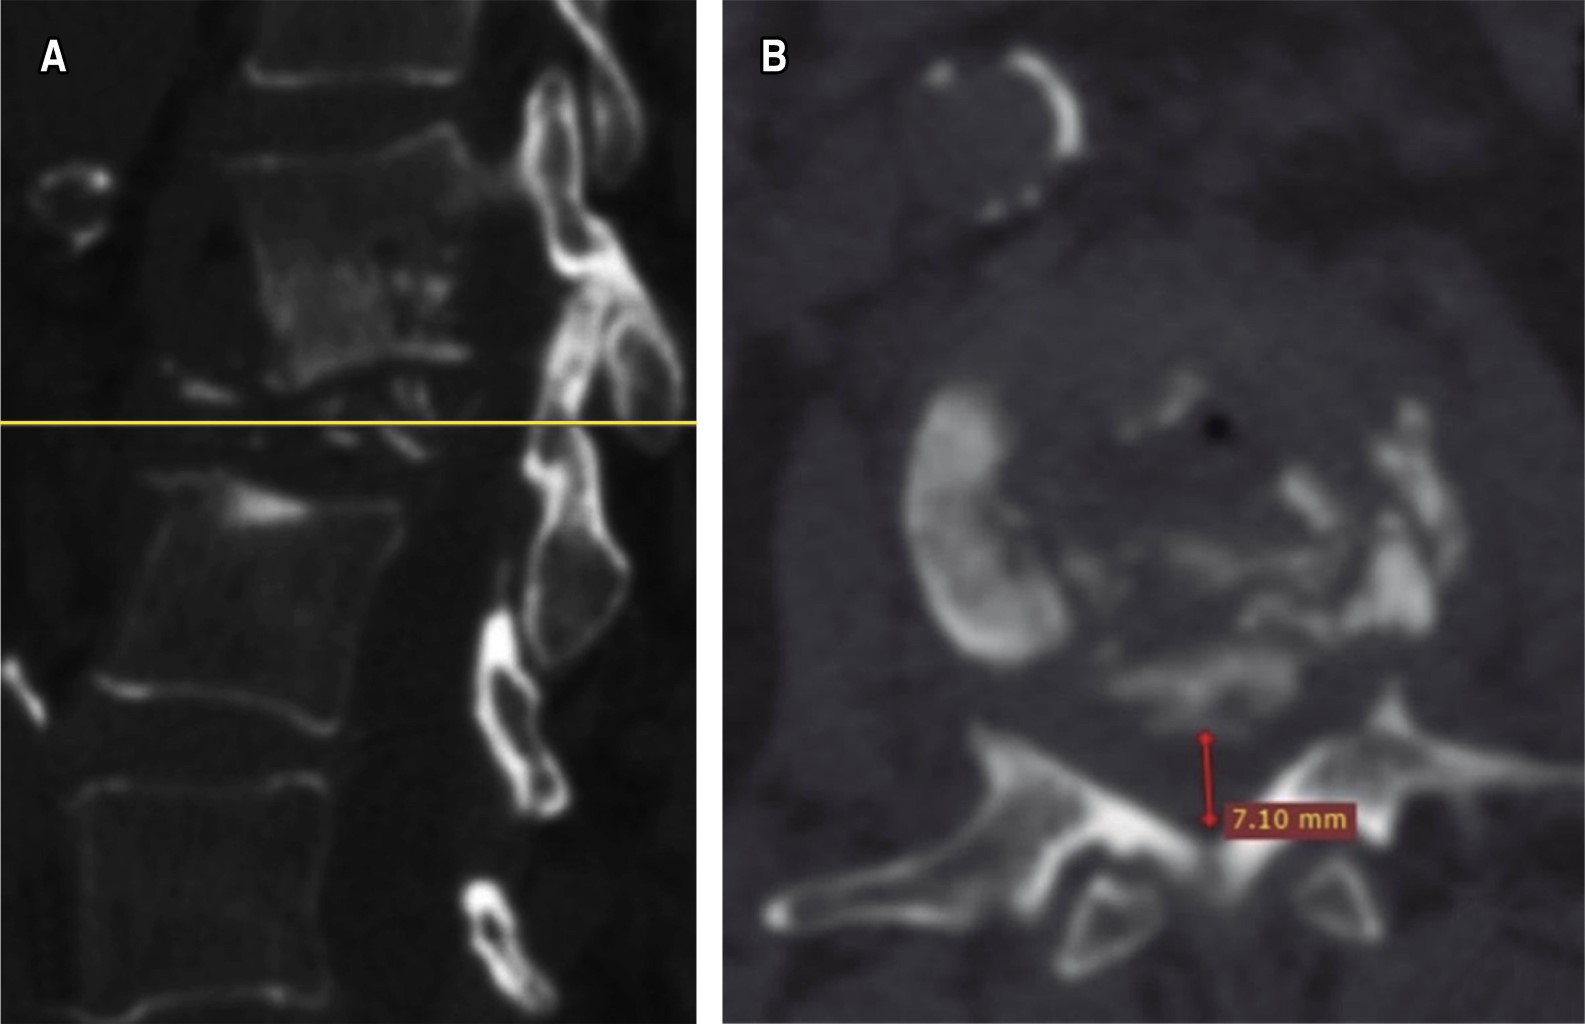

Introduction: brucellosis infection is considered a global public health problem, which is estimated in about 58% of the cases demonstrated with osteoarticular involvement. With a special predilection for involvement of the lumbar spine, in patients with carriers mostly with clear identifiable risk factors. Clinical case: we present the case of a 60-year-old female patient, who began suffering consistent with the presence of pain in the thoracolumbar region of long evolution, with poor response to conservative treatment which shows a progressive intensity, until conditioning loss of ambulation and prostration. A study protocol was performed, in which X-ray and computed axial tomography (CAT) were observed lytic lesion in the vertebral body L2, as well as hyperintense lesions with a tendency to invasion of the spinal canal in axial and sagittal T2 section. Conclusion: brucellosis continues to be an important pathology in our country, in our clinical case a surgical resolution similar to that reported in the international literature was performed, with the topic of the different tools available for such resolution.

Figure 1